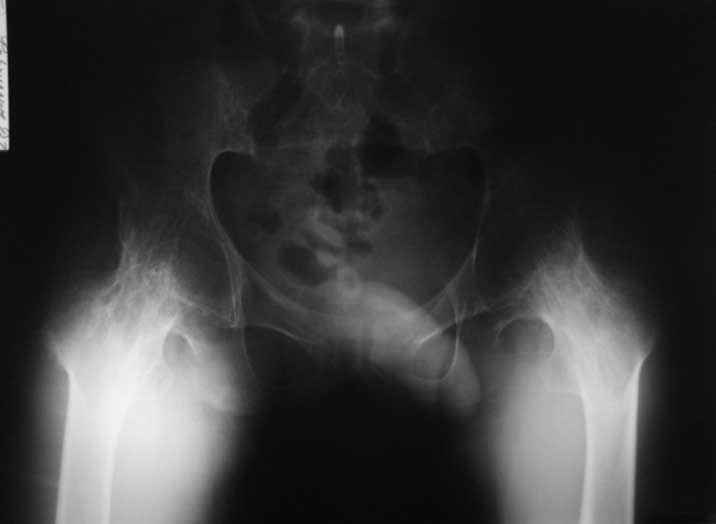

Уважаемые коллеги. пациент, страдает ревматоидным артритом с детства, ранее

костный анкилоз т/б суставов. 4 месяца назад THR левого т/б сустава, движения в т/б суставе

приличные - с/р 90/5/0, движения в коленном суставе ухудшились - с/р 120/45/0. В настоящее

время конечность неопорна из-за сгибательной кнтрактуры в к/с Вопросы о дальнейшей тактике